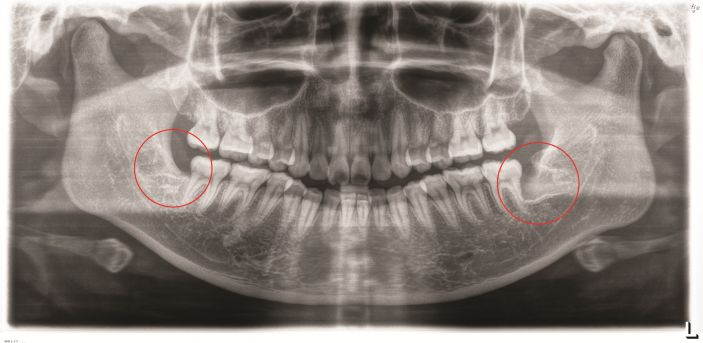

張主任講,微創拔智牙融合了多種先進的技術和理念,讓拔牙方式徹底告别盲目、暴力時代,具有這些優勢:1、個性化。術前通過CBCT明确患牙形态、埋伏深度及與下槽骨神經管、鄰牙的關系,分析骨阻力,設計、制定個性化的方案。2、創傷小。根據患牙特征,以減小創傷爲目的設計切口,采用超聲刀、切牙機等先進儀器設備,以小切口暴露牙冠,對患牙進行準确分割後經小切口逐一取出,告别傳統敲、鑿、劈、撬等一系列機械性操作,大幅度減少對正常組織的損傷。3、疼痛小、并發症少、恢複快。微創技術的應用,大幅減少智牙拔除的疼痛以及并發症,加快了術後的恢複。

△智牙拔除後。